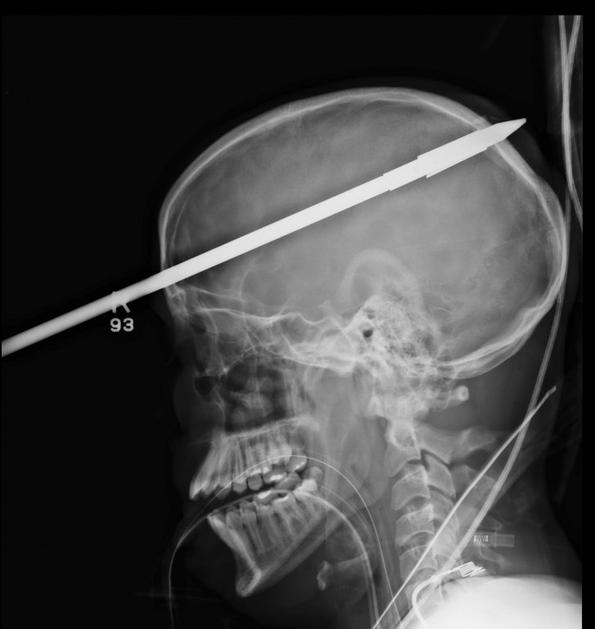

Glavo mu je preluknjala harpuna

Yasser Lopez